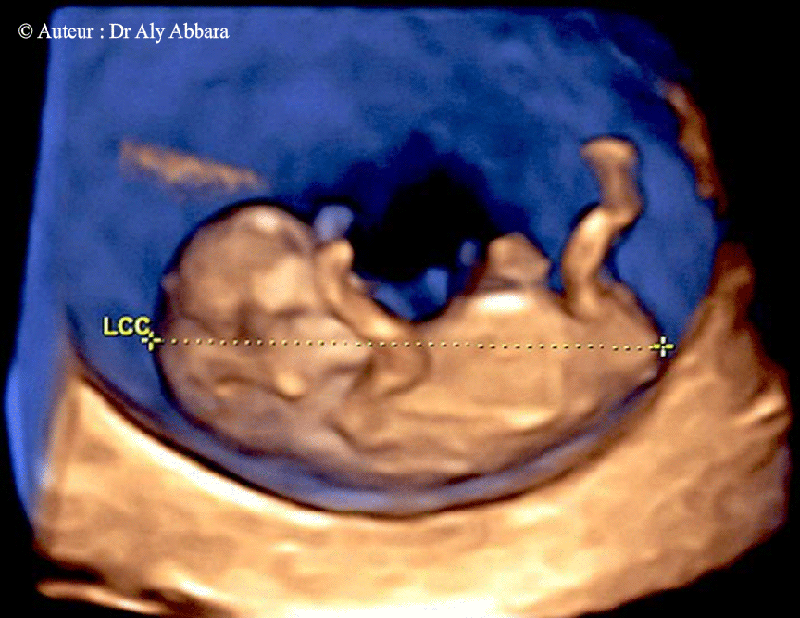

| Les conditions nécessaires pour obtenir une mesure valable de la longueur crânio-caudale afin de déterminer la date du début de grossesse. |

- Critères de qualité de la mesure de LCC sont :

- il est fortement recommander de déterminer la date du début de la grossesse par le recours à la mesure échographique de la longueur crânio-caudale fœtale (LCC) entre (11+0SA et 13+6SA) ce qui correspond à une mesure de la (LCC) située entre 45 et 84 mm.

- La coupe fœtale doit occuper > 50 % du champ de l'image.

- La coupe fœtale est sagittale.

- La position fœtale est neutre (ni en hyper-flexion ni en hyper-déflexion).

- L'extrémité céphalique fœtale est dégagée.

- L'extrémité caudale fœtale est dégagée.

- Les

curseurs sont biens placés.